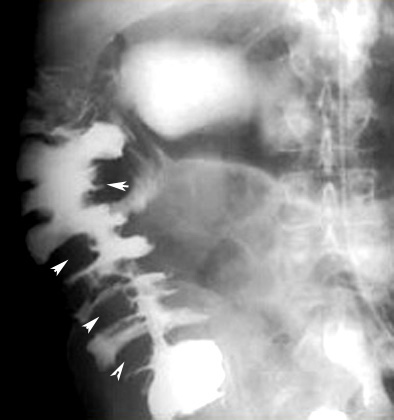

Ischemic colitis

Findings:

• Shows defects along the cecal margin

• "Thumb printing"